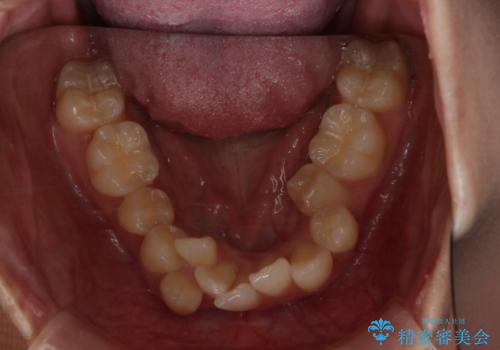

がたつきが強いガチャ歯。埋伏歯抜歯+矯正。すごいところに犬歯が埋まっていたのを抜いてワイヤー矯正治療

- 歯のがたつきを主訴に来院されました。

がたつきの強さから4本抜歯の必要性がありましたが、右上の歯は犬歯が一本埋まっており、乳歯がある状態でした。